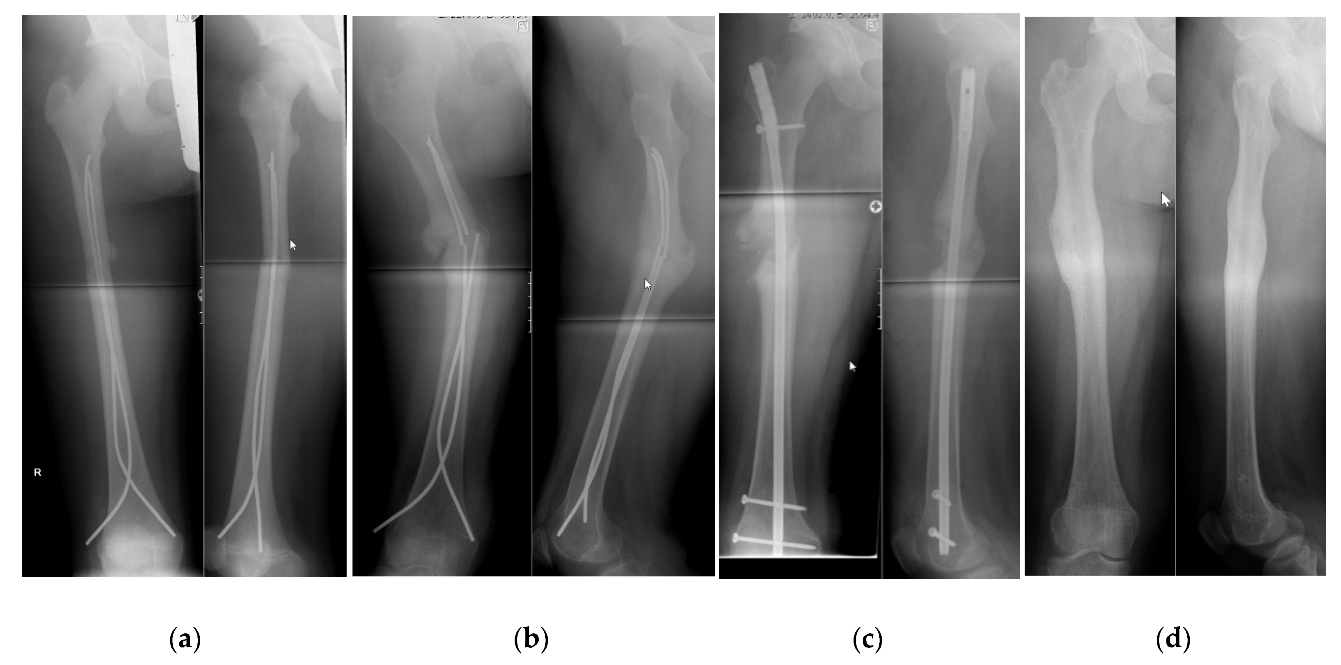

Children Free Full Text Health Related Quality Of Life After Adolescent Fractures Of The Femoral Shaft Stabilized By A Lateral Entry Femoral Nail Html